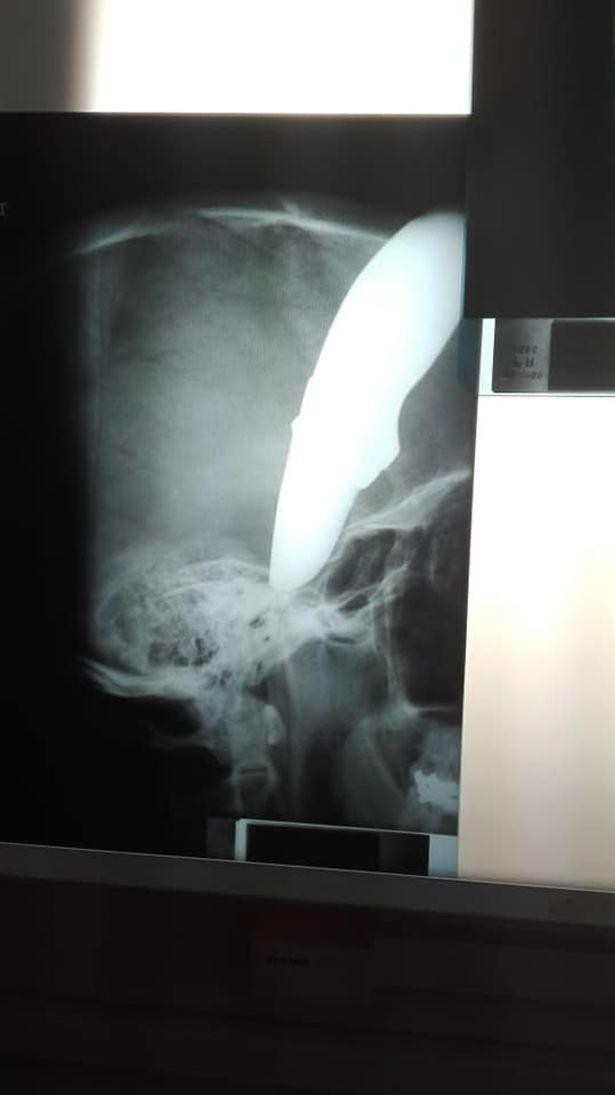

Con dao dài 15cm xuyên thủng sọ và nằm chặt trong não Shaun trong khi hai tên cướp cố giằng lấy chiếc xe đạp. Bất chấp vết thương chí mạng trên đầu, Shaun kiên quyết chống trả và thành công đánh đuổi hai tên cướp.

"Anh ấy rất may mắn vì con dao đã bị cong khi va chạm với xương sọ và lưỡi dao đâm xuống dưới chứ không xuyên vào não. Bệnh nhân rất may mắn vì con dao không đâm đúng chỗ để có thể gây chết người", bác sĩ cho biết.

Con dao bị cong khi đâm vào xương sọ

Bức ảnh Shaun chảy máu cùng con dao trên đầu, bình tĩnh đứng ở bệnh viện kèm hình chụp X-Quang lan truyền nhanh chóng trên mạng.